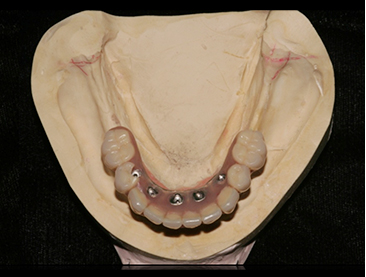

Fully edentulous clinical cases